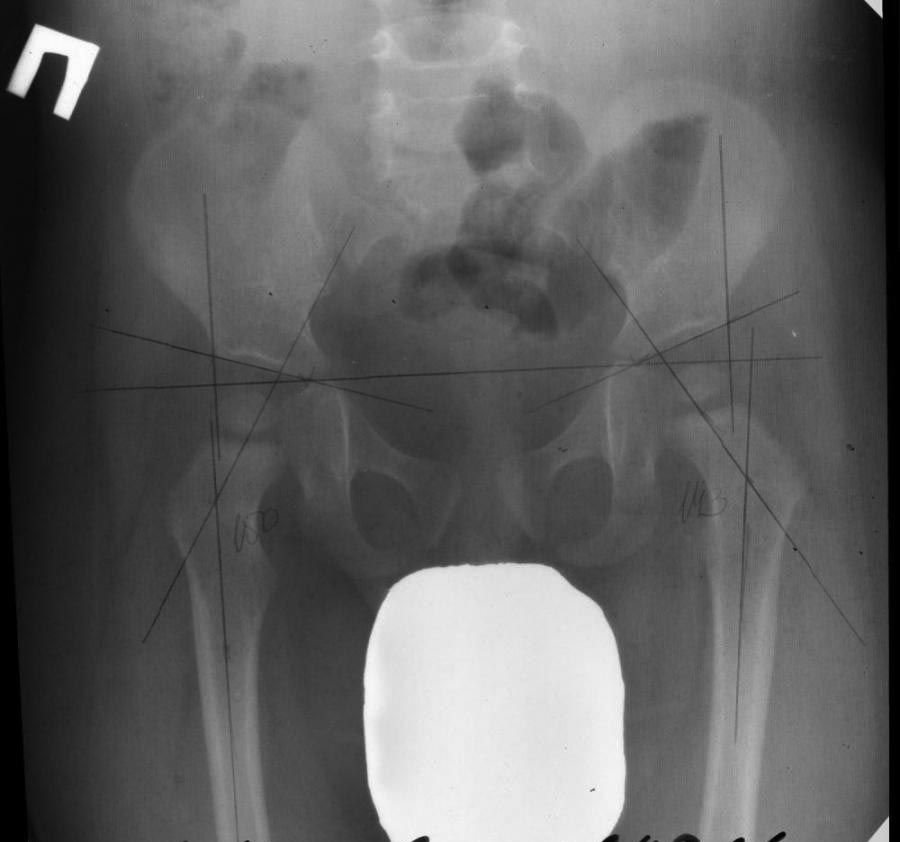

Доброго дня,господа.Прошу Вас проконсультировать: моему сыну 1,5 года. В 8 месяцев по настоянию ортопеда участкового сделали рентген ТБС (до этого УЗИ и осмотр не выявляли патологии).

В интерпретации данного снимка мнения врачей разделились радикально: от полной нормы до выявления недостаточного окостенения и размера ядер головок и рекомендации по ношению шины виленского. Мы выбрали среднее мнение и делали массаж, ЛФК, ФТЛ (2 курса). Сейчас в 1,5 года (23.09.2016) повторно по рекомендации того же ортопеда сделали контрольный Rh снимок.У ортопеда еще не были. Заключение рентгенолога: децентрация головок, задержка процессов окостенения головок, вальгусная деформация шеек обеих бедренных костей. Оба заключения и оба снимка прилагаю. к этому сообщению прилагаю снимок от 23/09/2016. Прошу высказать мнение по таким вопросам: 1) есть ли у нас проблемы с ТБ суставами? 2) Каковы вообще нормы размеров и положения этих головок. почему так расходятся мнения врачей? 3) не имеет ли места дефект укладки на снимке из-за которого врач некорректно интерпретирует картину?Заранее благодарю за помощь!с уважением,Мави Багдасарьян

Сообщение с аналогичной темой я отправила ранее. Здесь отправляю снимок ТБС от 2015 года для сравнения и картины в динамике

наши действия это не поиски болезни, а попытка разобраться. по данному снимку мы получаем противоречивые мнения докторов, как я писала. в описании снимка врач рентгенолог поставила диагноз дисплазия. хочется услышать мнения других врачей.